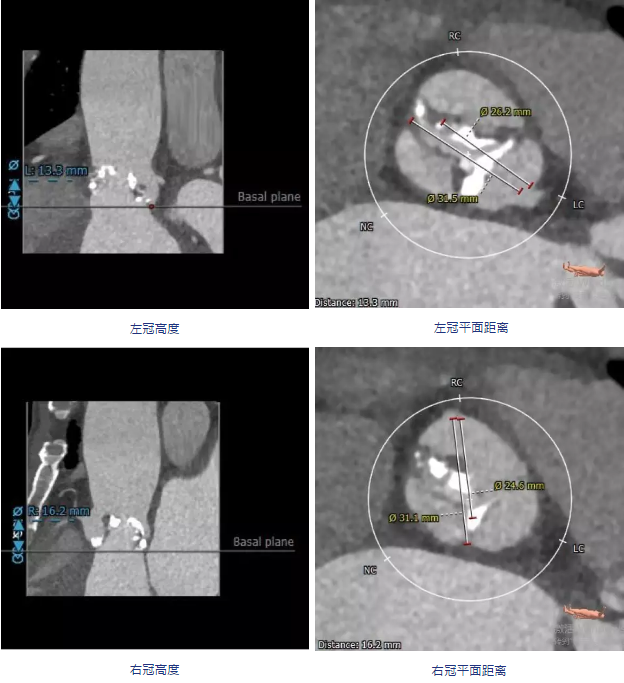

CT分析:

颈动脉入路输送系统模拟情况

建议术中球囊扩张确认冠脉风险,瓣膜型号推荐VenusA-Valve29号瓣膜,备选VenusA-Valve26号瓣膜。